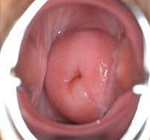

治疗后